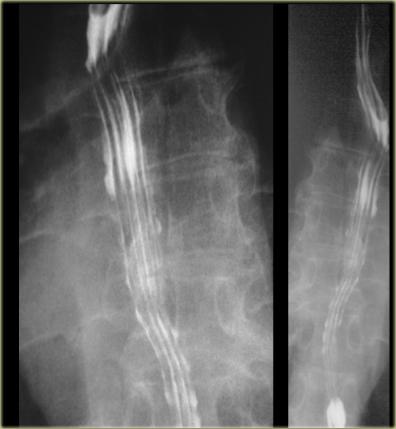

- Thực quản dạng ống kéo dài đến ngay trên cơ hoành.

- Sự giãn phình dạng bóng ở đoạn thực quản xa được gọi là tiền đình, tương ứng với cơ thắt thực quản dưới được xác định bằng đo áp lực.

Sự giãn phình này được thể hiện rõ nhất khi nín thở ở thì hít vào hoặc nghiệm pháp Valsalva.

Không nhầm lẫn hình ảnh này với thoát vị khe hoành.